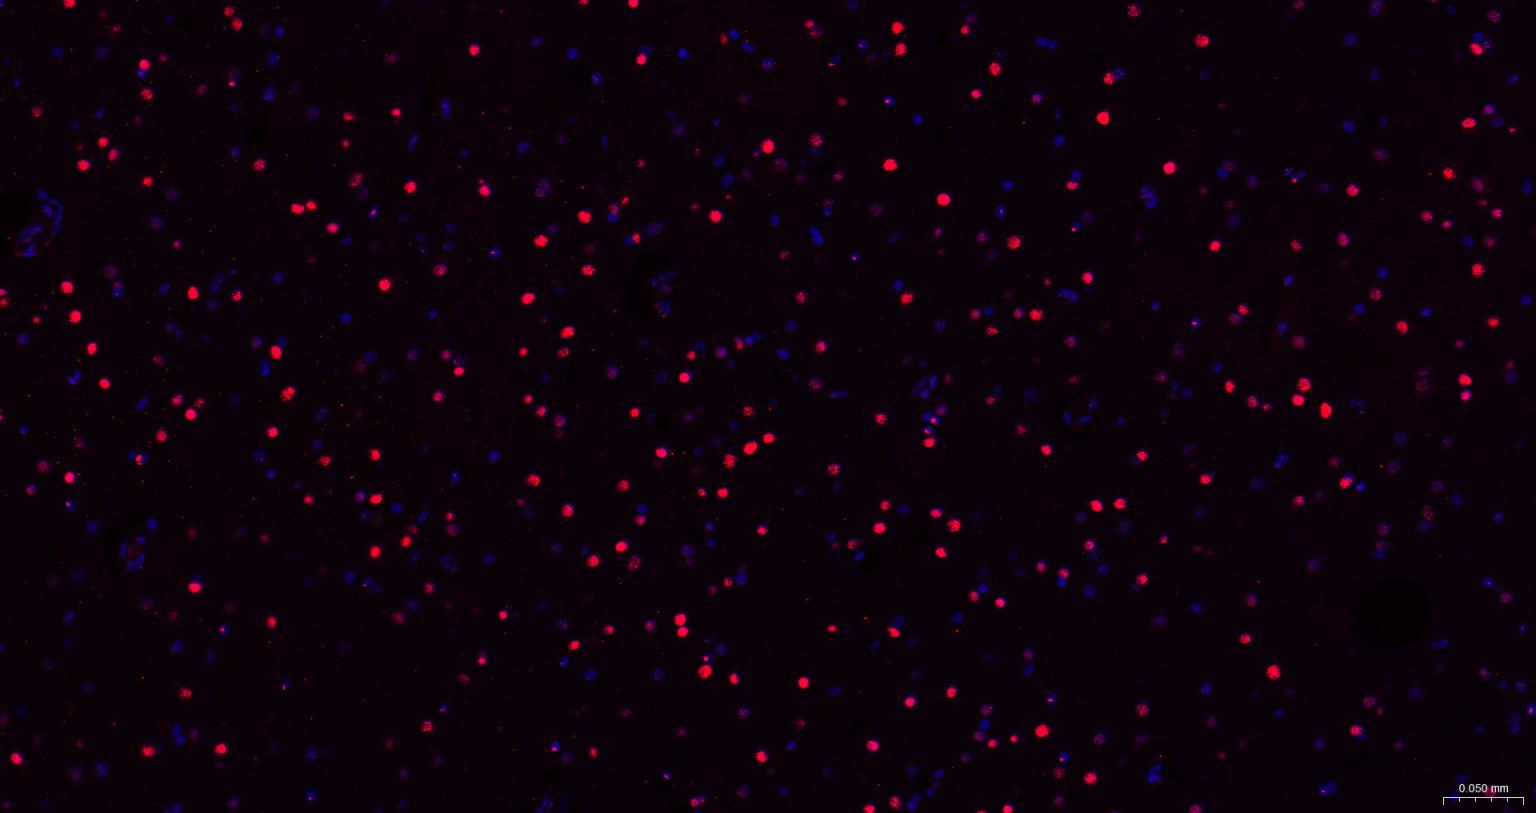

Paraformaldehyde-fixed, paraffin embedded Human Cerebrum; Antigen retrieval by boiling in sodium citrate buffer (pH6.0) for 15 min; The section was incubated with SOX1 Monoclonal Antibody, Unconjugated (bsm-54625R) at 1:200 overnight at 4°C. Followed by conjugated Goat Anti-Rabbit IgG antibody (Red, bs-0295G-BF594), DAPI (blue, C02-04002) was used to stain the cell nuclei.